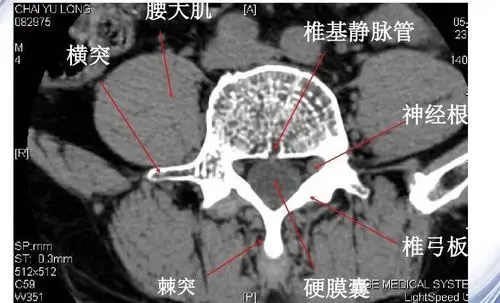

中枢神经系统影像解剖图谱连载3腰椎mri概论t1wi轴位解剖图